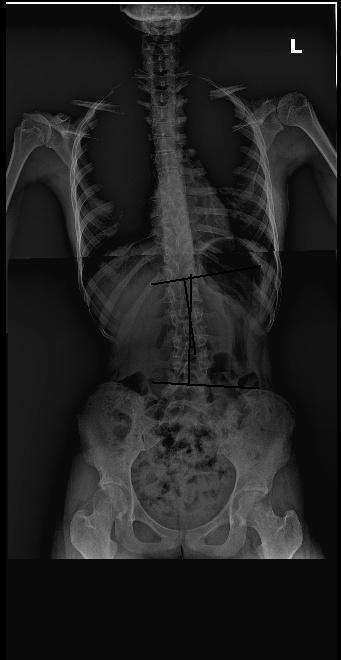

척추 측만증 치료 사례 3

치료 전 9도

치료 후 5도

분석 : 치료 전 9도의 측만에서 치료 후 5도의 측만으로 4도 정도의 호전을 보였습니다.

치료 : 주 1회 , 3개월간 추나요법 및 매선 치료를 하였습니다. 평상시 허리 통증과 만성적인 턱관절 통증을 호소하였는데 이 증상도 더불어 좋아졌습니다. 척추 주변 근육이 매우 약해서 현재 바태운동 즉 체형교정운동을 통해 근력 증강 중이며 바르게 앉기 연습 중 입니다.